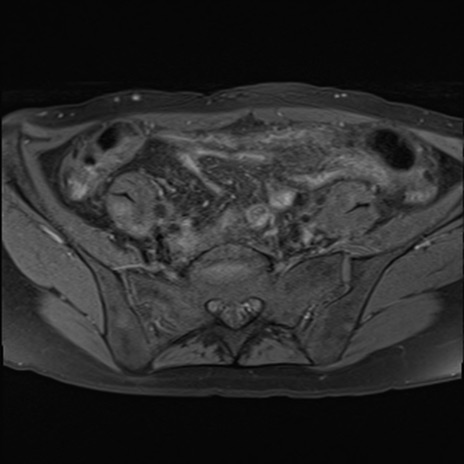

症例39 脂肪抑制T1WI(横断像)

MRI(4日後)

T1WI(横断像)